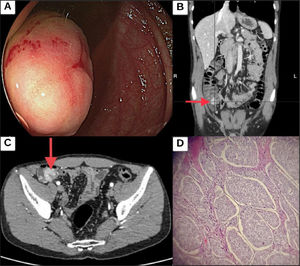

The patient was now studied for chronic diarrhea, ordering blood and stool tests (Table 1). Esophagogastroduodenoscopy was within normal parameters. The histopathologic study reported non-atrophic congestive gastropathy, with no villous atrophy in the duodenum. Colonoscopy revealed a 30 mm exophytic lesion in the cecum, with an ulcerated surface and friable to manipulation (Fig. 1A). Contrast-enhanced abdominopelvic tomography identified a lesion on the medial and inferior edge of the cecum, with focal thickening measuring 18 mm, necrosis, and paracecal lymph nodes (Fig. 1B and C).

(A) Colonoscopy showing a 3 cm lesion in the cecum. (B and C) Coronal and axial views of contrast-enhanced CAT scans, showing a lesion at the medial and inferior edge of the cecum, characterized by an 18 mm focal thickening of the wall, with endoluminal extension. (D) Histopathologic section of a grade 2, well differentiated neuroendocrine tumor, showing an epithelial tumor with nest-shaped growth, cells with moderately pleomorphic nuclei, and lax or dense chromatin, as well as mitosis and scant cytoplasm. The tumor is developed in a vascularized stroma and shows infiltration through all the layers of the colon, extending beyond the serosa.

The patient then underwent right hemicolectomy with lymph node resection. His preoperative chromogranin A level was 117 ng/mL (NV < 85 ng/mL), and his somatostatin level was 6 ng/mL (NV < 10 ng/mL), which were within normal parameter ranges. The histopathologic study reported a well-differentiated grade 2 neuroendocrine tumor (NET) (pT2, pN1, pM0) with invasion in all layers, extending beyond the serosa, and exhibiting lymphovascular permeation. The tumor was positive for chromogranin +++, synaptophysin +++, and Ki-67 (3–20%), and metastasized to 2/28 lymph nodes (Fig. 1D).